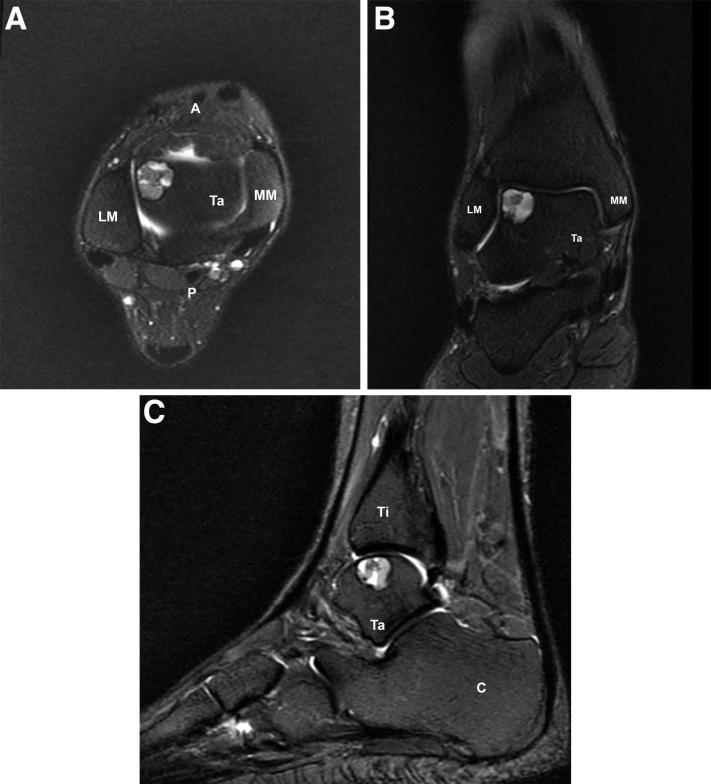

镶嵌成形术的新概念:覆盖有细胞化支架的自体骨膜圆柱移植体

A New Concept of Mosaicplasty: Autologous Osteoperiosteal Cylinder Graft Covered With Cellularized Scaffold.

A concern regarding osteochondral autograft transfer for chondral defects is donor-site morbidity of the knee, the most common source of the autograft. To avoid the drawbacks of osteochondral autograft transfer, a cylindrical osteoperiosteal graft harvested from the iliac crest covered by a same-sized cylinder of hyaluronic acid-based polymer scaffold pretreated with bone marrow aspirate concentrate and transferred to the chondral defect recipient site in the exact size for restoration of the subchondral bone and the articular cartilage.

摘要